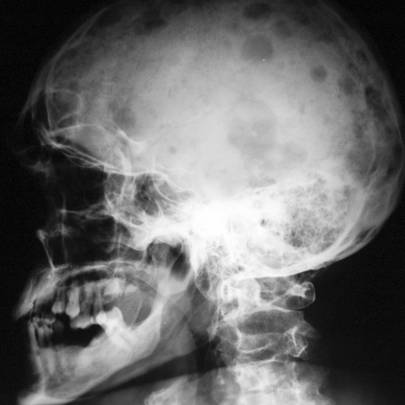

Визуализационные методы исследования для определения скелетных повреждений и параспинальных повреждений костного мозга (рентген, компьютерная или магнитно-резонансная томографии).